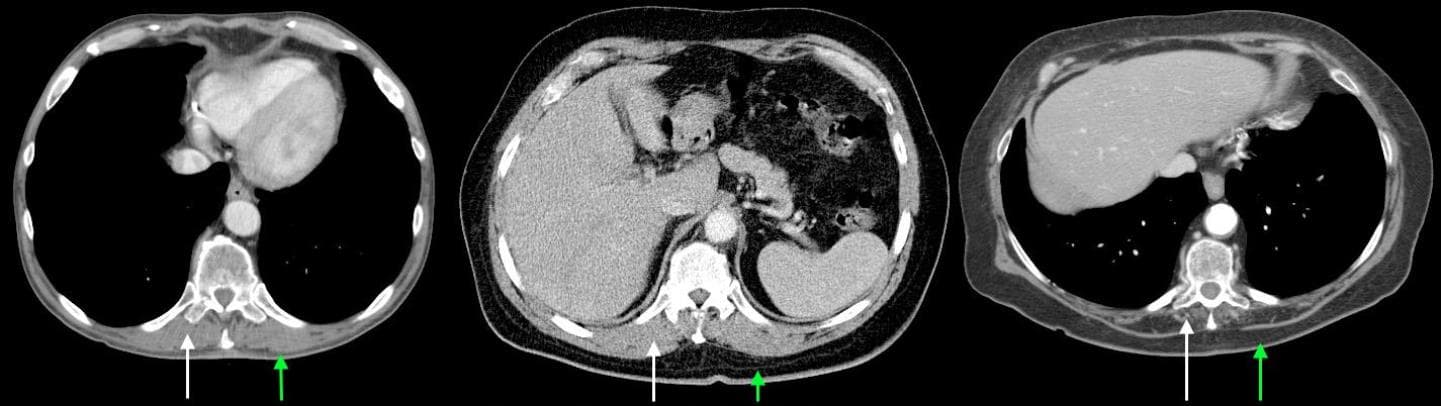

In conjunction with colleagues at the University of Michigan, we are also measuring patients' core muscle mass on a standard CT scan, since low muscle mass likely correlates with frailty. We recently found that patients with a low BMI are at increased risk for postoperative complications after lung resection, and these patients are also more likely to be frail.

The current frailty interest group at the University of Chicago is comprised of experts in geriatrics, physical therapy, nutrition, respiratory and muscle metabolism, and surgery. In addition to frailty screening and exercise interventions, we are beginning to look at molecular processes that are correlated with weakness and low muscle mass. These findings will be correlated with muscle mass/density measurements from CT scans. Identifying these mechanisms may help us develop personalized treatments.